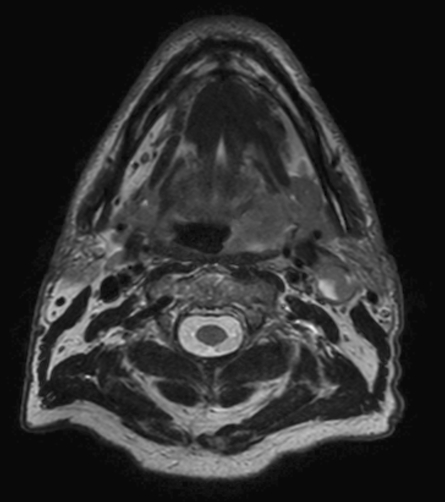

A 75-year-old male with oropharynx squamous cell carcinoma in the left tonsil region with extension into the soft palate, caudal border lower tonsil region, no midline crossing. On the left side in the neck there are also three enlared lymph nodes on level 2 and 3 with central necrosis and signs of limited extracapsular extensionn, T2N2b. Patient underwent MRI simulation in the radiotherapy (5-point) positioning mask in Ingenia MR-RT 3.0T using the Flex coils in combination with integrated Posterior FlexCoverage coil.

T2w TSE mDIXON (water only)